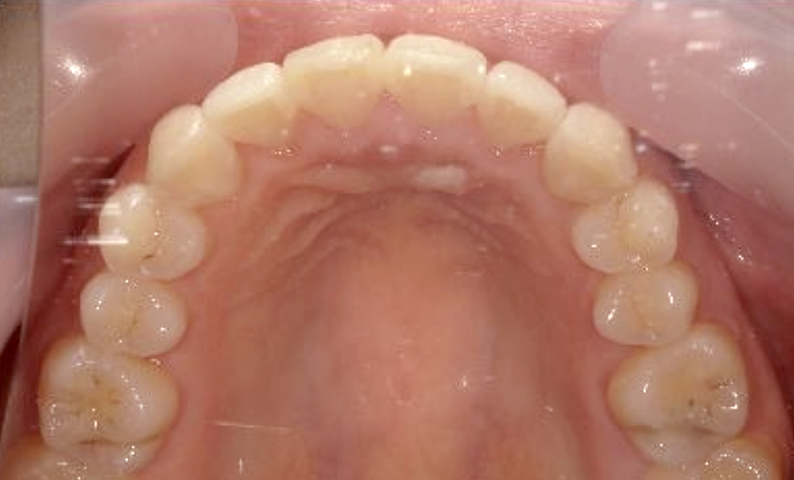

症例_023 上顎だけの部分矯正

治療期間:9ヶ月金額:30万円+税女性前歯のガタガタ上の前歯だけ

| Before | After |